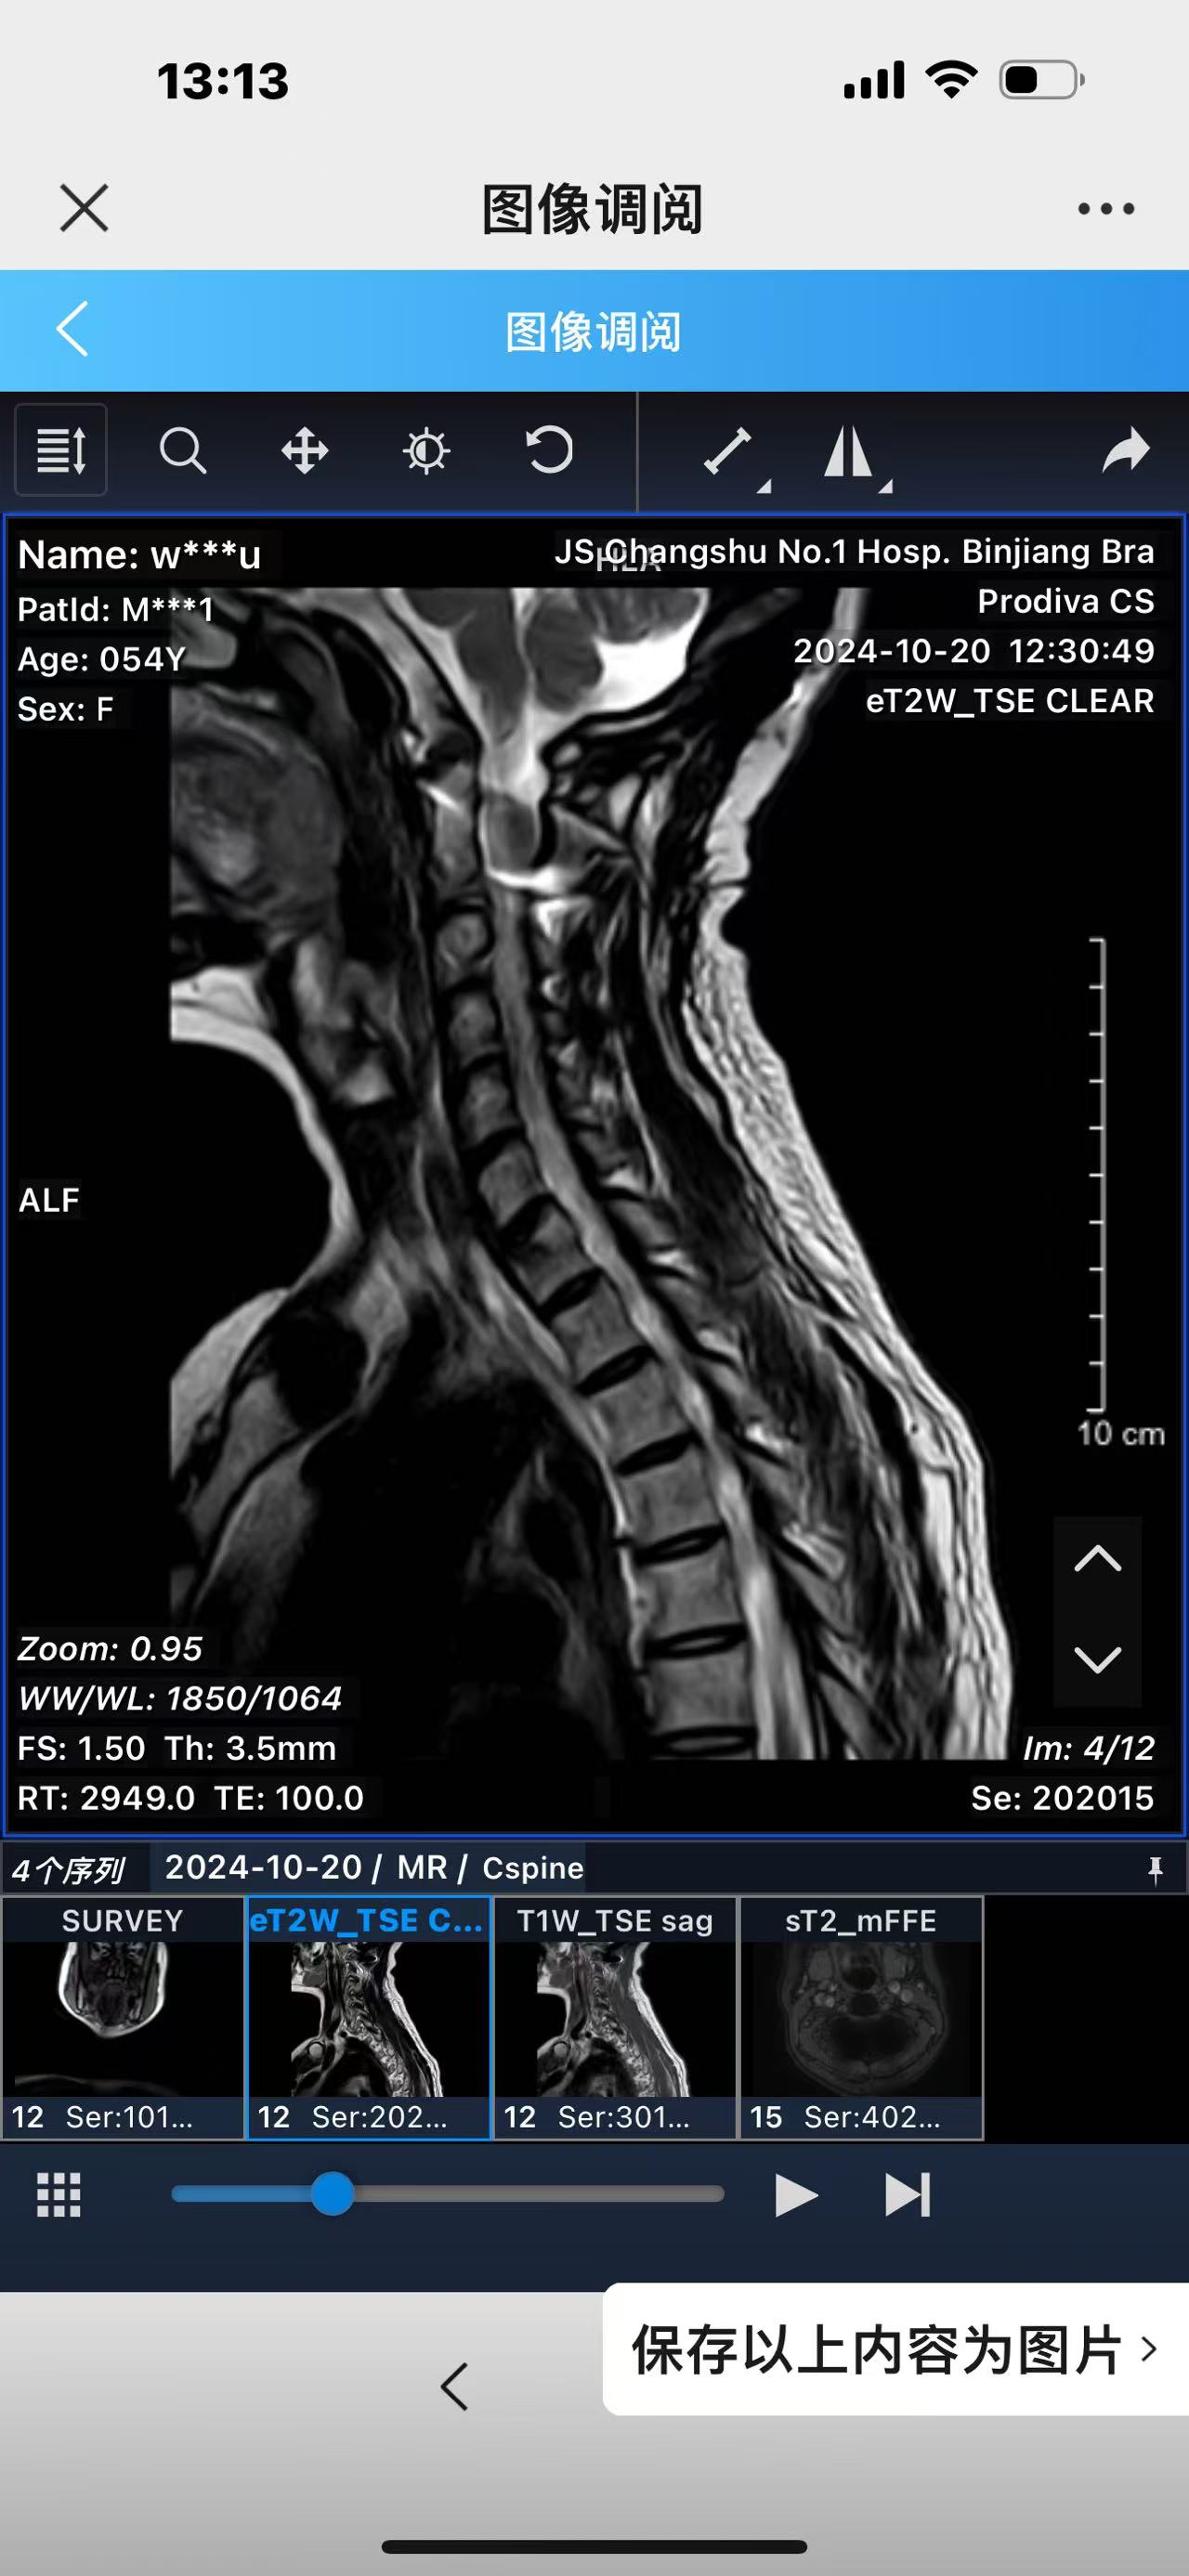

• 2024.10.20,复查,对位良好,偶尔会肩甲骨酸,坐下就不酸。